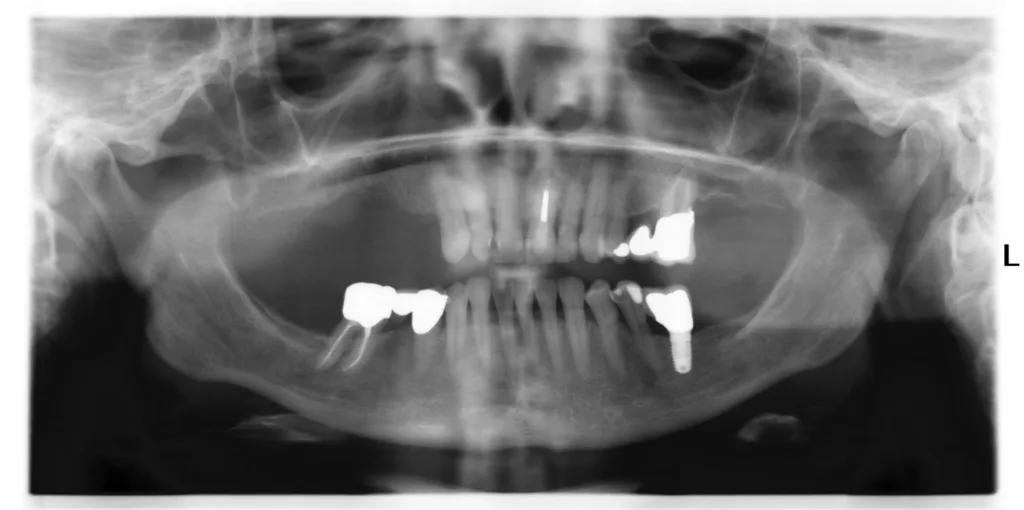

- Fortgeschrittene Alveolarkammatrophie im Unterkiefermolarenbereich (häufig) (Abb. 23 bis 29)

Transversale Implantatknochenplateaus werden während der Implantation chirurgisch korrigiert (GOÄ 2730), um periimplantäre Trichter und prothetisch lange Abutments mit infektanfälliger Gingiva zu vermeiden (Abb. 30). Die prothetische Versorgung des Unterkiefers erfolgt festsitzend unter Verwendung axial verschraubter, nicht zementierter, unverblockter Einzelkronen (Hygiene, Zementierungsschäden, Periimplantitis). Die Integration in den Praxisalltag gelingt nur mit Fokus auf die Gewebebiologie unter Abkehr von der rein mechanistischen Versorgungslehre und Verblockungstheorie.

Durchmesserreduzierte (< 4 mm), schmale Implantate mit transgingivaler Einheilung (Minis) sind aufgrund ihrer Materialeigenschaften (Bruch) und begrenzten prothetischen Versorgungsmöglichkeit und Kompatibilität auf Einzelindikationen bei multimorbiden Patienten/-innen mit zahnlosem Unterkiefer, erhöhtem OP-Risiko (fortgeschrittener Diabetes, Gerinnungserkrankungen etc.) und eingeschränkten Hygienemöglichkeiten limitiert [17].